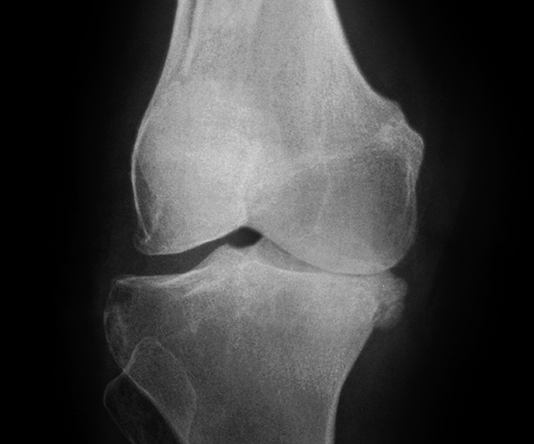

2. Giai đoạn 2: Thoái hóa khớp gối độ 2

Hình ảnh của khớp gối trên phim X-quang: Khe khớp hẹp nhẹ, có gai xương nhỏ.

Thoái hóa khớp gối giai đoạn 2 vẫn là giai đoạn nhẹ

Giai đoạn 2 vẫn được xem là giai đoạn tiến triển nhẹ, xem trên phim X-quang có thể thấy kích thước bề mặt sụn khớp vẫn chưa có sự thay đổi nhiều. Bao hoạt dịch khớp vẫn hoạt động bình thường, cung cấp đủ dịch khớp để nuôi dưỡng sụn và bôi trơn ổ khớp, giúp các đầu xương hoạt động được trơn tru. Mặc dù vậy, bệnh nhân vẫn có thể xuất hiện một số triệu chứng như đau mỏi ở khớp gối sau khi vận động nhiều hoặc khi làm việc quá sức, làm việc sai tư thế; cứng khớp khi trời lạnh hoặc do ít vận động khớp.